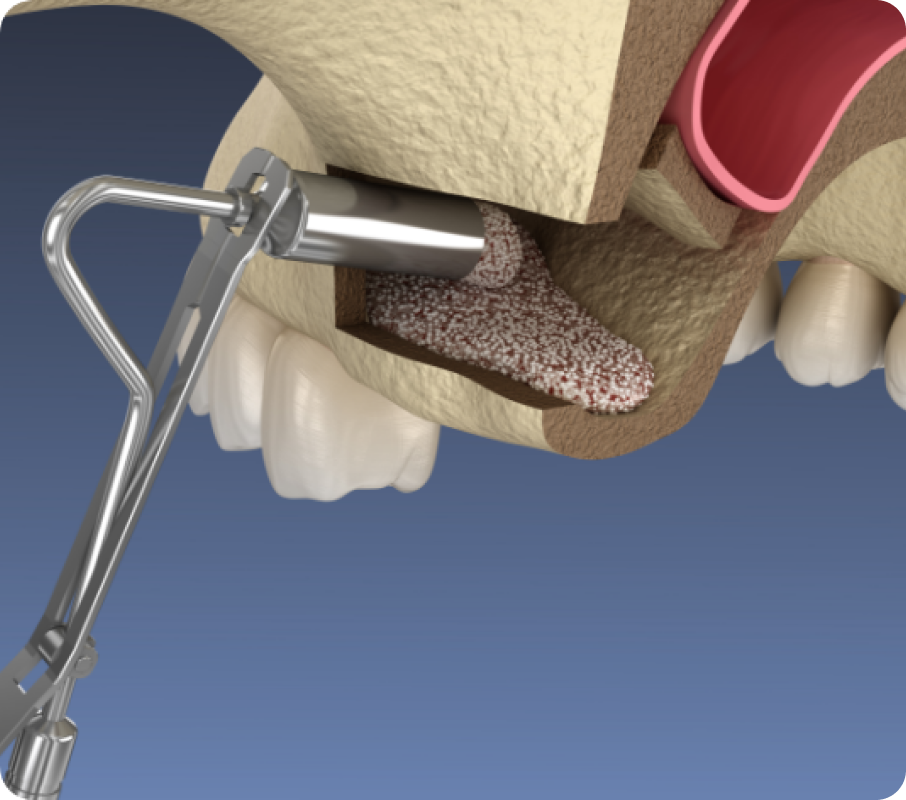

당일 사랑니 발치

당일 사랑니 발치

당일 사랑니 발치

사랑니는 영구치열을 방해하고 관리가 어려워 충치, 염증 등 문제를 일으킵니다. 신경까지 고려하는 당일 사랑니 발치로 빠르고 안전하게 해결합니다.